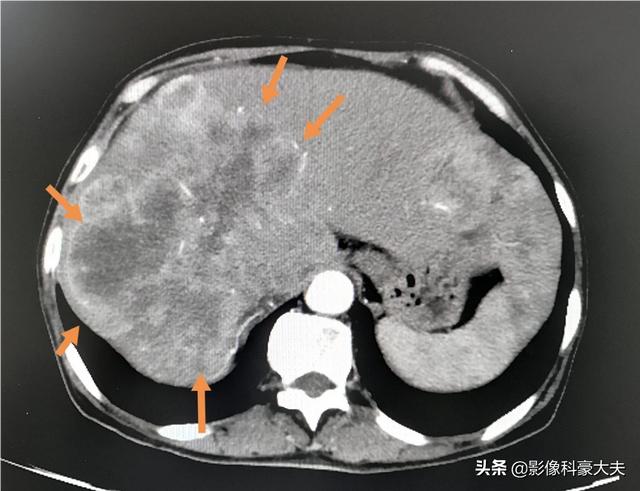

Les métastases hépatiques géantes multiples comme celles-ci peuvent progresser en peu de temps si elles ne sont pas contrôlées ou si elles sont insensibles au traitement.

À un stade avancé, le cancer du poumon peut présenter de multiples métastases dans divers organes du corps. Le cancer du poumon métastase souvent dans le cerveau, le foie et le système vertébral squelettique, et les métastases cérébrales peuvent provoquer une hypertension intracrânienne. L'espace étant limité dans le cerveau, la propagation des cellules cancéreuses peut entraîner une hernie cérébrale et une hypertension intracrânienne, qui mettent en danger la vie du patient. Les métastases vertébrales peuvent entraîner des fractures pathologiques, une compression des nerfs, conduisant à la paralysie et même à la mort. Des métastases hépatiques multiples, qui peuvent entraîner un dysfonctionnement du foie et une insuffisance hépatique.

4. métastases tumorales, défaillance de plusieurs organes :Des métastases à différents organes peuvent se produire à un stade avancé du cancer du poumon, causant de grandes souffrances aux patients. Les patients atteints de cancer du poumon peuvent former des métastases dans des organes tels que la plèvre, le cerveau, les glandes surrénales, le foie, les os, le péricarde et ainsi de suite, provoquant une défaillance de plusieurs organes, qui peut entraîner la mort du patient.